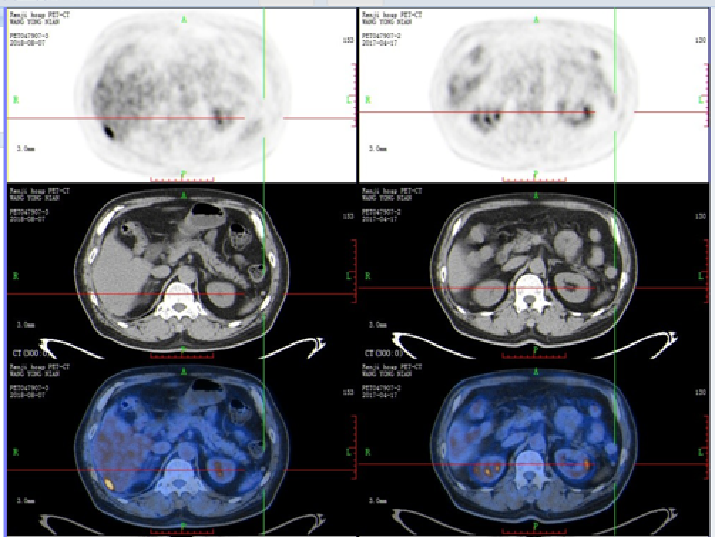

二线治疗:FOLFIRI+贝伐珠单抗

【贝伐珠单抗+FOLFIRI】2018-8-7 我院PET-CT提示直肠癌术后,吻合口FDG代谢未见异常,肝右叶转移瘤切除术后,脂肪肝,残余肝右后叶下段包膜下结节样FDG代谢异常增高(SUVmax 9.9),较前片新增,考虑肿瘤转移可能性大,双肺多发微小斑点、结节影,其中右肺上叶前段、后段两枚小结节(较大者直径约5mm,SUVmax 1.3)较前片新增,考虑为转移瘤可能。

2018-8-11 至 2018-10-11 日予以二线第1-12周期FOLFIRI方案联合贝伐珠单抗靶向治疗,4,8,12疗程评估后稳定。